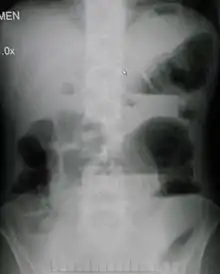

| Upright abdominal X-ray demonstrating a small bowel obstruction. Note multiple air fluid levels. | |

Radiological signs of bowel obstruction include bowel distension and the presence of multiple (more than six) gas-fluid levels on supine and erect abdominal radiographs. Ultrasounds may be as useful as CT scanning to make the diagnosis.[13]